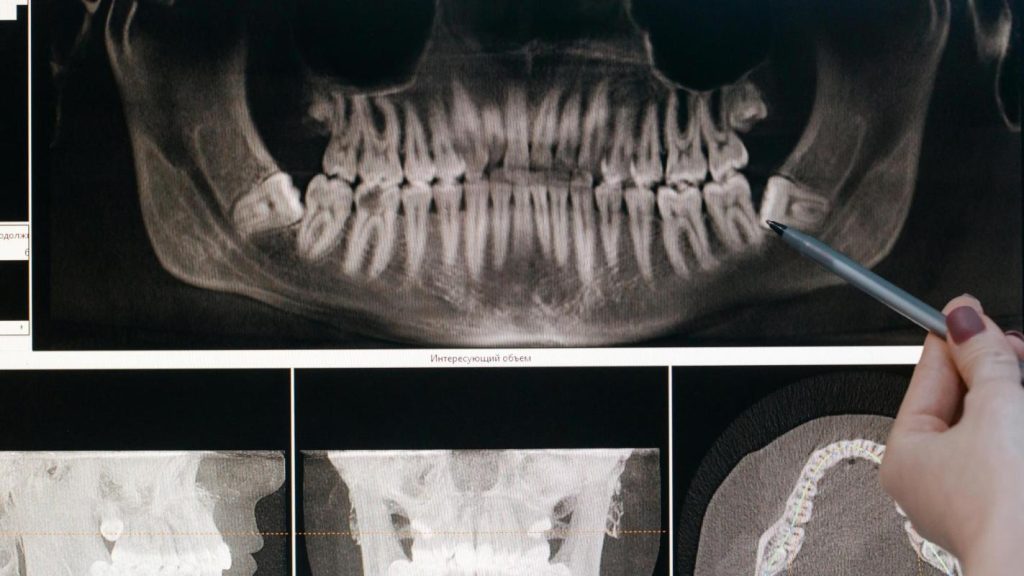

Las bacterias utilizan los azúcares de la dieta y forman ácidos. Con el tiempo, este proceso puede ir debilitando las partes duras del diente. Afecta, por ejemplo, al esmalte, ya que sustrae minerales esenciales como el calcio y el fosfato, que son los encargados de mantenerlo resistente y fuerte. A esto se le llama desmineralización.

Sin embargo, en el proceso continuo de desmineralización y remineralización, pueden aparecer manchas blancas opacas en la superficie del diente que está pegada a la encía. Estas manchas representan el primer signo clínico de caries dental (la caries dental no siempre comienza como un “hueco”).

La coloración se debe a que la pérdida de minerales altera la forma en que la luz se refleja en el diente, razón por la que se aprecian estas zonas blancas y opacas. Se podría decir que las manchas blancas son las pistas e indicios con los que el diente avisa. Este mensaje nos advierte que los ácidos están ganado terreno y han comenzado a debilitar su estructura.

Se dice que una lesión de caries está activa cuando continua progresando, ya que las bacterias siguen produciendo ácidos que atacan el esmalte y la dentina. Es como si el diente estuviera atrapado en una lluvia de ácidos, sin refugio para sanar. Por otra parte, la lesión de caries inactiva es la que no ha avanzado. Aunque el tejido dental está afectado, ya no hay actividad bacteriana ni pérdida de minerales.